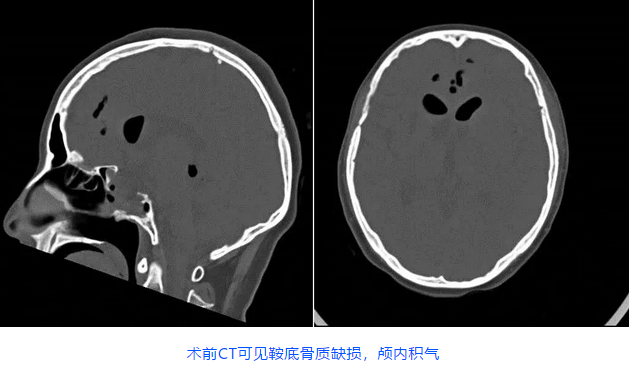

三博神经内镜中心任铭主任了解病情后,判断患者很可能是迟发性脑脊液鼻漏,鼻漏逆行感染引发了颅内感染。王女士入院后化验提示脑脊液白细胞升高,蛋白增高,葡萄糖和氯化物降低,头颅CT可见鞍底骨质缺损,颅内积气,核磁显示右侧枕角少量积脓。检查结果证实了任铭主任的判断,患者脑膜炎、颅内感染,导致意识障碍。而发生颅内感染的原因就跟脑脊液鼻漏有关,鼻腔的病菌和外界的气体经漏口进入了颅内。

手术修补常见的有开颅及经鼻两种入路。患者既往两次手术史,头颅CT提示鞍底缺损,蝶窦开放,第二次行显微镜经鼻入路垂体瘤切除术,粘膜瓣应该仍然尚存,因此这次手术可行内镜下经鼻入路脑脊液漏修补术,争取一次修补成功,防止以后脑脊液鼻漏再次发生,然后再给予患者积极抗感染治疗才能有效。